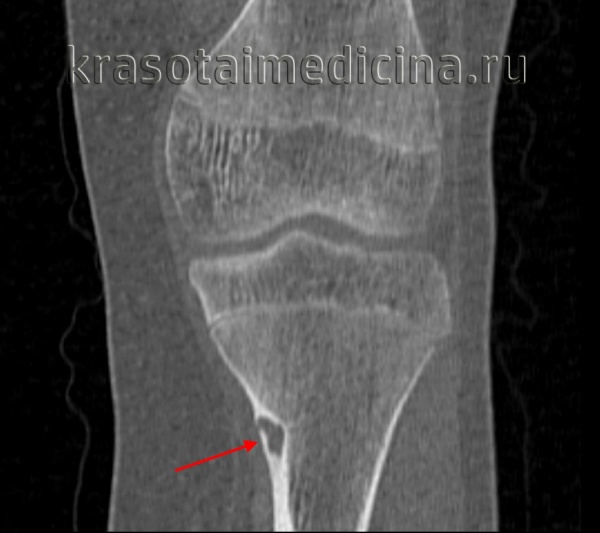

- Рентгенография кости. На снимках визуализируется кистообразные изменения или неоплазия в виде «мыльных пузырей» в метафизарной зоне. Признаки общего остеопороза отсутствуют, вокруг измененного участка может просматриваться остеосклероз. Границы доброкачественной ГКО более четкие, но из-за местно-агрессивного роста при значительном размере возможно появление «костного козырька». Выраженная периостальная реакция нехарактерна. Злокачественная остеокластома имеет нечеткую структуру. На снимках рано обнаруживается разрушение кортикального слоя.